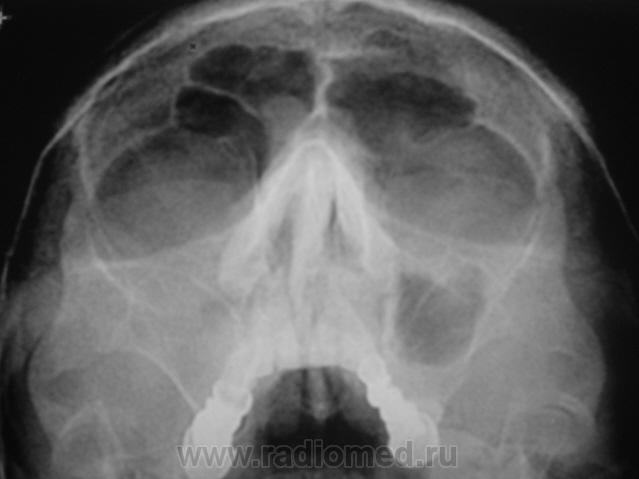

Пациент второй.

Второй случай. уровень слева,субтотальное затенение справа.киста правой половины лобной.....